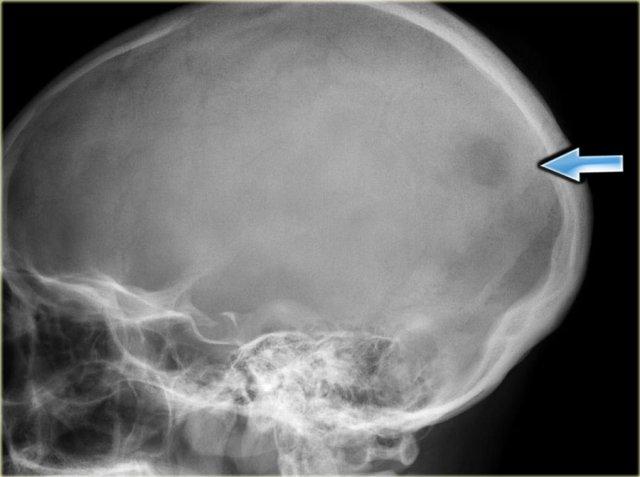

Ở bên trái là hình ảnh điển hình của u hạt bạch cầu ái toan trong hộp sọ dưới dạng tổn thương tiêu xương không rõ ranh giới.

Ở bên trái là một số ví dụ về U hạt bạch cầu ái toan (EG) với bờ không rõ ràng.

Có phản ứng màng xương đơn lớp hoặc đa lớp.